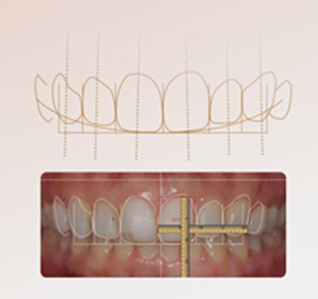

个性化托槽定制

通过先进数字辅助设计、制作及成像技术,量身定制符合个人牙齿特点的托槽,并能模拟出矫正后的预期效果。

“饱满笑线”的矫治

在牙齿正畸同时,关注笑线改变与侧颜重塑,让正畸不仅仅是矫正,更是一项关于牙齿的美学艺术。

“没有废招”的矫治

通过计算机辅助技术可以准确“预估”矫正效果。托槽均为个性化定制,可与直丝匹配使每颗牙齿按照既定的排牙设计移动到最终理想的位置,让矫正没有白走的路,每一步都算数!